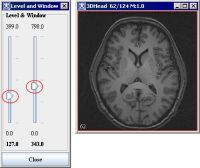

The Level and Window dialog box

Move each slider up or down to change the contrast of the image. The changes are immediately effective in the image.

2. Click Adjust Window and Level. The Level & Window dialog box appears.

3. In the dialog box, move each slider up or down to change the contrast of the image. The changes are immediately effective in the image. Click Close when done.